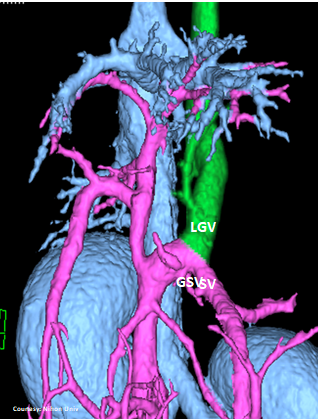

Does LEFT GASTRIC VEIN (LGV) enter the GASTROSPLENIC VEIN (GSV)?

WEISSE 2022